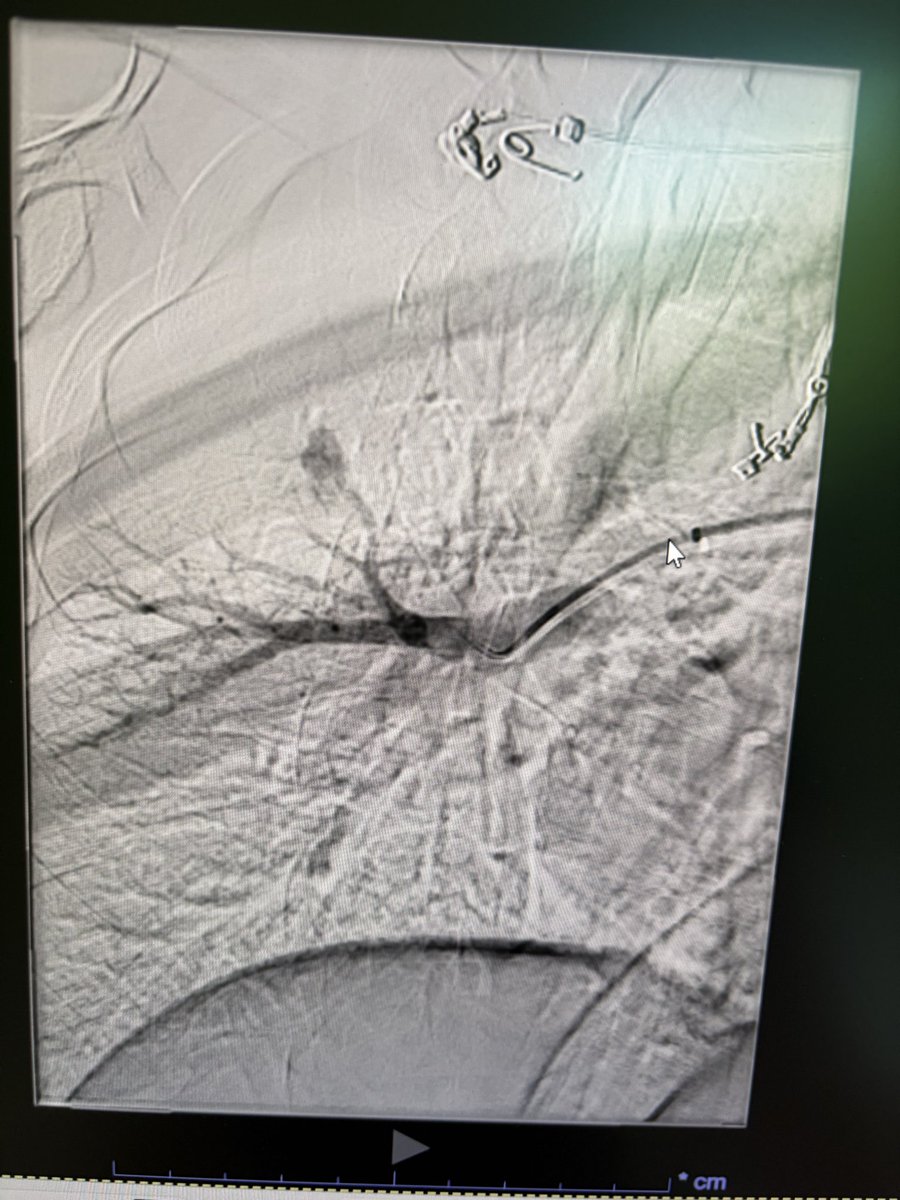

Left superior thyroid angiogram in this patient with multinodular goiter and retrosternal extension. Angiogram shows the necklace anastamosis between the two superior thyroid arteries and also with left inferior thyroid artery. @hospital_kims @ISVIRIndia @SIRRFS @JVIRmedia